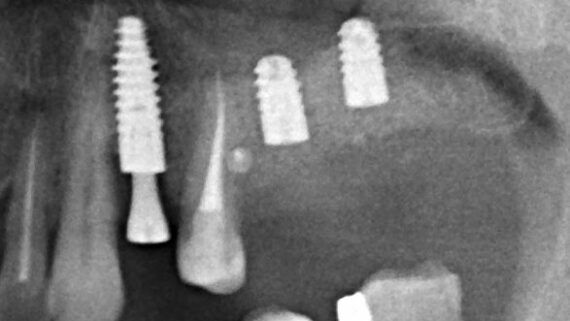

Думаю, все согласятся с тем, что последовательные хирургические вмешательства, вроде «удаление зуба — синуслифтинг — имплантация — формирователь десны» будут сопровождаться намного меньшей вероятностью осложнений, чем если бы мы провели удаление зуба, имплантацию с синуслифтингом и формированием десны за один этап. Так вот, если в случае со здоровыми людьми целесообразность подобных усложений еще можно обсуждать, то в контексте темы лечение по принципу «всё и сразу» — верный путь к пиздецу к проблемам.

Иными словами, даже в благоприятных условиях, когда, на первый взгляд, можно провести ту же немедленную имплантацию, лучше пойти наиболее консервативным путем: сначала удаление зуба, затем через 2 месяца — имплантация с закрытым ведением имплантата, затем еще через 3-4 — установка формирователя десны и протезирование.

Да, такой консервативный и осторожный подход значительно, иногда в два раза, удлиняет время стоматологической реабилитации, но тут поспешишь — людей насмешишь. Напомню, что ошибки в лечению людей на остеопорозной терапии стоят очень и очень дорого.

Третий момент имеет значение для имплантологического лечения — это грамотное и тщательное планирование предстоящих операций, в т. ч. с использованием хирургических шаблонов.

Точные и хорошо спроектированные хирургические шаблоны для имплантации позволяют не только правильно позиционировать имплантаты, тут мы и без сопливых справляемся. Намного важнее, что их использование сокращает время хирургической операции и снижает её травматичность путем уменьшения размера операционной раны. Мы не теряем время на этап позиционирования и примерок, у нас нет необходимости в большой ране — мы можем сделать разрез точно под лунку имплантата. Конечно, такие технологии хороши и для полностью здоровых пациентов, но в случае с людьми, принимающими бисфосфонаты, их использование более, чем целесообразно.

Еще раз подчеркну, что проводить имплантологическое лечение и наращивание костной ткани пациентам, принимающим бисфосфонаты МОЖНО, если осторожно. Более того, с точки зрения рисков развития осложнений, имплантация выглядит более безопасной, нежели удаление зуба. Хотя бы потому, что ушить рану при отсроченной имплантации проще, чем лунку после удаления зуба.

Ежу понятно, что в этом случае исключаются все варианты открытого ведения установленного имплантата: немедленная имплантация, немедленное протезирование, формирование десневой манжеты и т. д. Только заглушка и глухие швы после имплантации.

Вторым, уже упоминавшимся нюансом является отказ от лечения по принципу «всё и сразу» даже в ситуациях, когда это возможно:

Другими словами, если в нормальных условиях мы бы объединили синуслифтинг и имплантацию в одно хирургическое вмешательство, то в случае лечения пациентов, принимающих бисфосфонаты, лучше делать всё последовательно.

Третий пункт, — и мы про это тоже говорили, — это приоритет малотравматичных, пусть и компромиссных по результату методов лечения. Например, если в тех же нормальных условиях мы будем следовать имплантологическому правилу №2, то при лечении пациентов на антиостеопорозной терапии от него можно отступить в разумных пределах: использовать имплантаты меньших длины и диаметра, установить их в компромиссное положение и т. д.